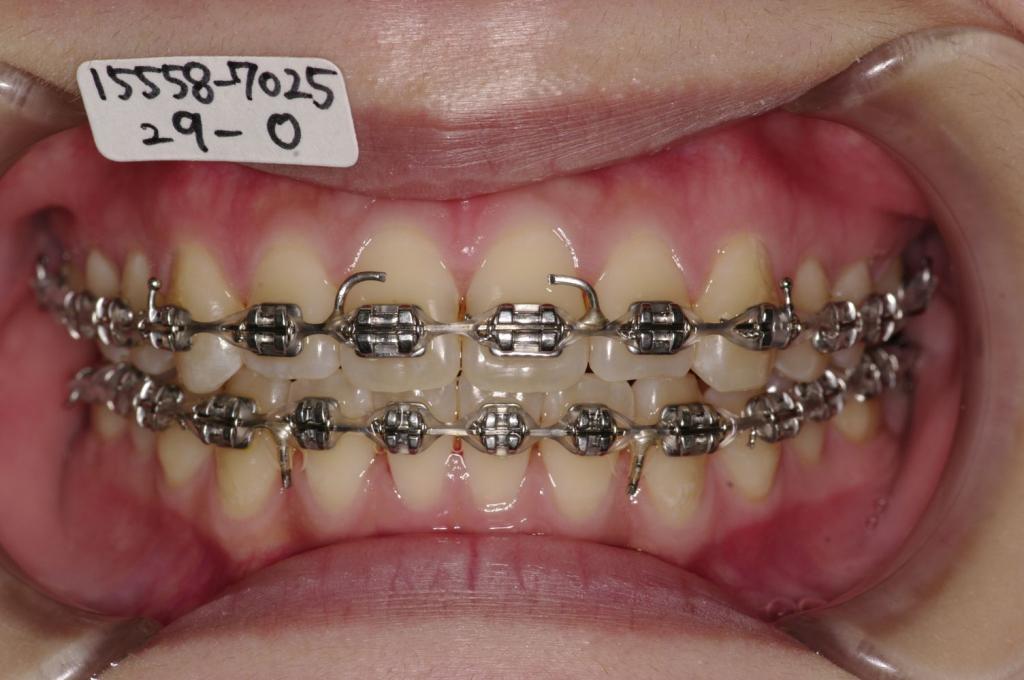

治療方法および装置:マルチブラケット装置

装置写真

治療前

前歯、出っ歯・開咬の矯正治療前口内写真NO.1078

治療後

前歯、出っ歯・開咬の矯正治療後口内写真NO.1078